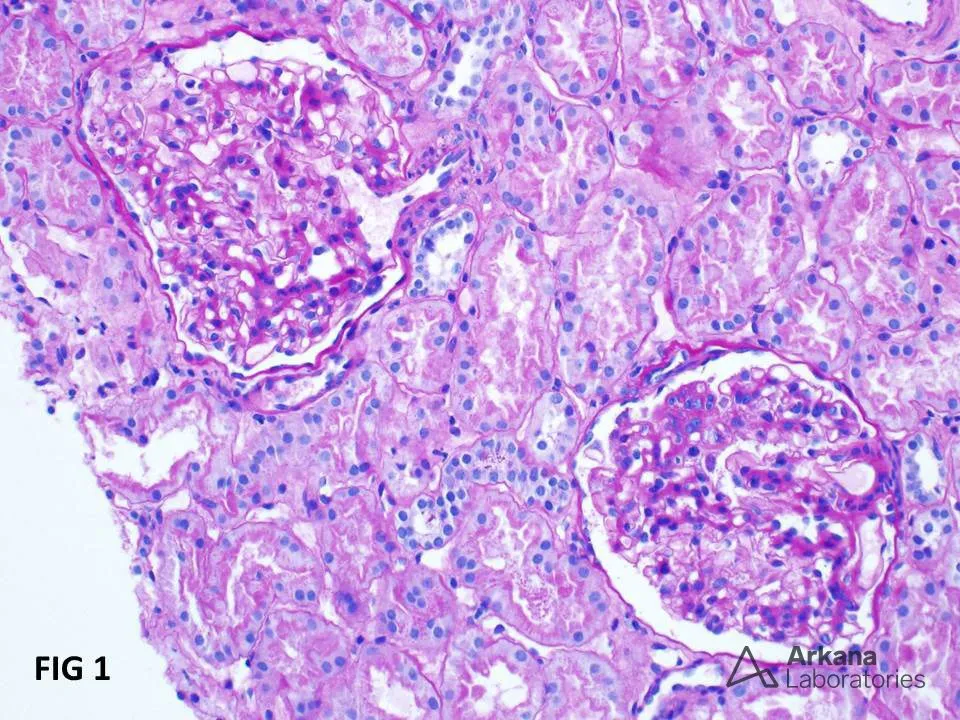

glomerulopatias